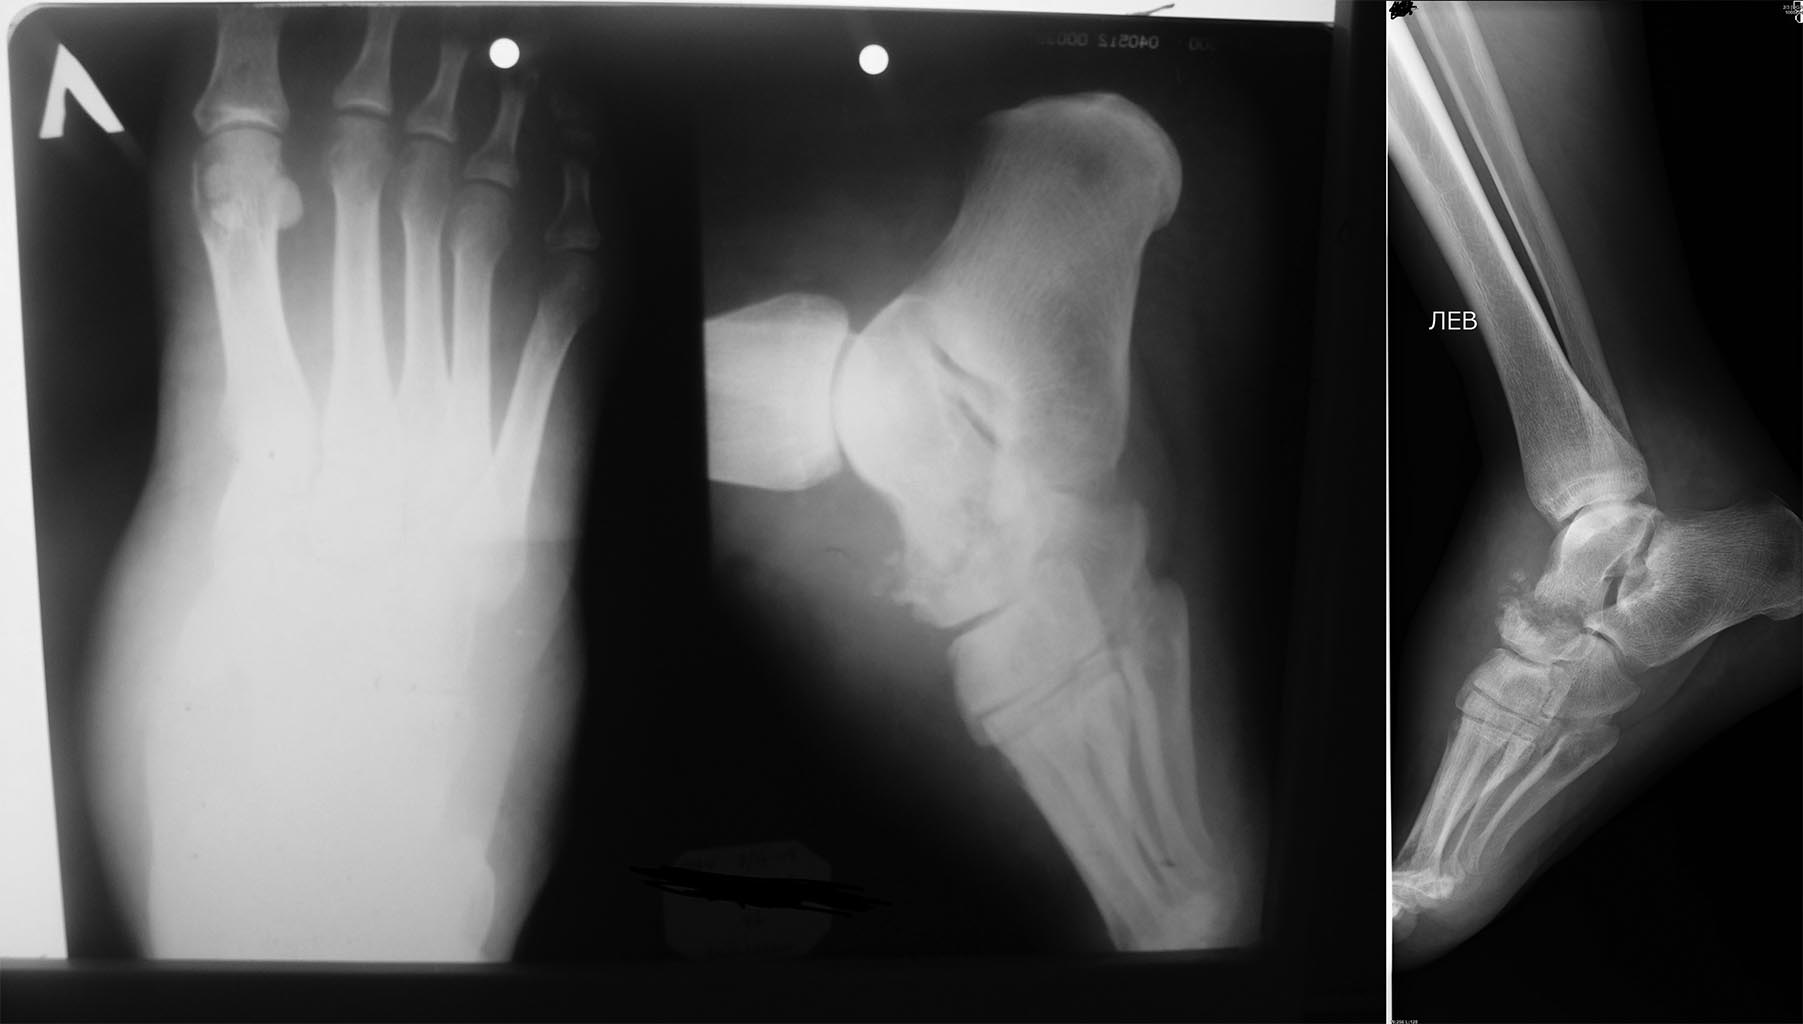

Уважаемые коллеги помогите пожалуйста поставить диагноз.

Пациент с жалобами на боль в стопе, усиливающуюся при ходьбе, объемное

образование тыла стопы 6,0*6,0 см. Болеет около 1 года. Осмотрен

онкологом онкодиспансера - без онкопатологии ( по результатам биопсии).

Консультация тубостеолога - ТБС не обн. При исследовании обнаружили

новообразование дистального метаэпифиза большеберцовой кости и бедренной

кости. Помогите пожалуйста определиться с диагнозом и методом лечения.